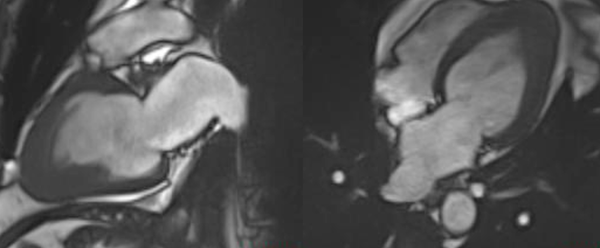

Cardiomyopathy